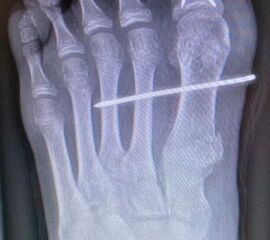

Zusätzlich schränken Wachstumsfugen die Wahl der Osteosynthese ein. Eine die Fuge kreuzende Osteosynthese ist ausschließlich mit Kirschner-Drähten möglich (Abb. 3).

Abb. 3 a-j: Beispiel einer Calcaneusverschiebeosteotomie mit offenen Wachstumsfugen und der entsprechenden Osteosynthese mit Kirschner Drähten. Lokalisation der Osteotomie (a), Lage der Fräse (b-d), Drahtlage mehrere Ansichten (e-h), Heilung der Osteotomie 4 Wochen postoperativ und Entfernung der Drähte (i-j).

Zum Lesen der Bildbeschreibung und zur Vollansicht bitte die Bilder anklicken. Bilder: A. Helmers.